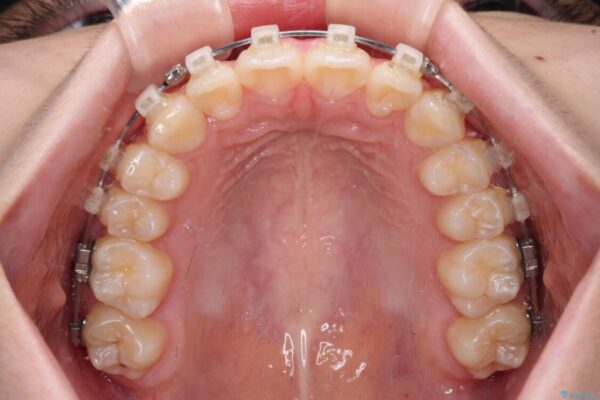

治療後

• インビザラインは使える自信がない ワイヤー装置にて矯正治療 治療後画像